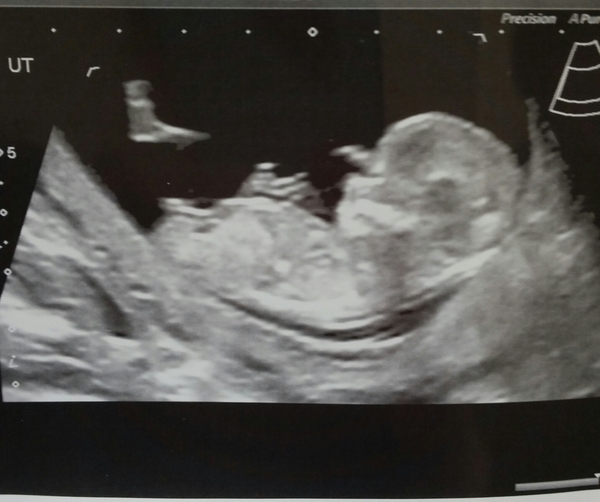

Well had my scan and all seemed fine. Nuchal fold measurement was 1.7mm which from what I gather is right in the middle of average. Midwife then doing bloods for some reason was dead against the down syndrome blood test and really tried to talk me out of it. No idea why but we ended up back and forth for ages and she relented in the end... It is my choice after all. Baby wasn't very good and got into some awful positions so lots of left hand side lying, jiggling and coughing to get a decent nt measurement.